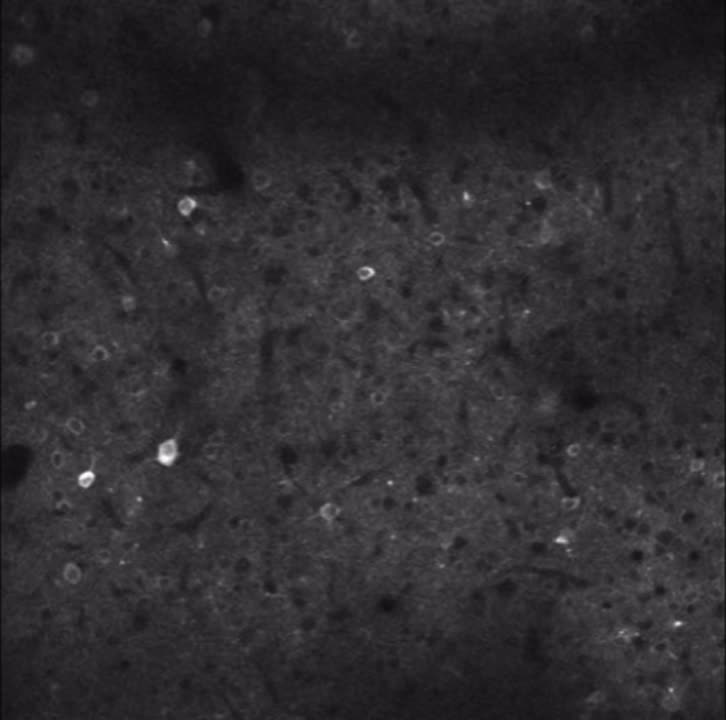

Videoen du ser i toppen av saken er fra en musehjerne. De lysende punktene er nerveceller i et område av hjernen som lyser opp når musa nærmer seg objekter den vet hvor er.

Området disse nervecellene ligger i heter retrosplenial cortex. Da forskerne undersøkte nervecellene der nærmere, oppdaget de to svært viktige ting.

– For det første var det noen av disse nevronene som faktisk forutsa hvor et objekt befant seg før musene var fysisk nær objektet. For det andre fortsatte disse nevronene å være aktive selv når objektet var fjernet.

I studien har musene kunnet bevege seg og utforske objekter i mørket. Mens musene utforsket omgivelsene, brukte forskerne avanserte laserskanningsmikroskoper for å måle aktiviteten til tusenvis av individuelle hjerneceller i hjernen til musene.